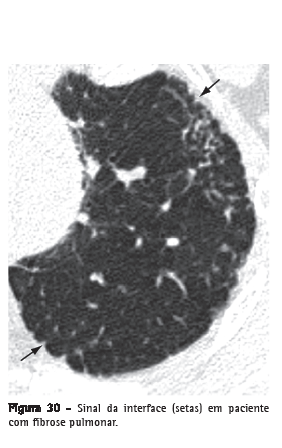

Interface

Superfície de separação entre duas estruturas ou espaços. Quando duas estruturas torácicas com diferentes densidades radiológicas se encontram, seus limites são nítidos. Por exemplo, vasos com densidade de partes moles em contato com a densidade de ar do pulmão arejado circunjacente. O "sinal da interface" define a irregularidade das margens entre diferentes estruturas intratorácicas, tais como vasos, brônquios e superfícies pleurais, em geral em decorrência de doença intersticial que causa fibrose (Figura 30).(3)